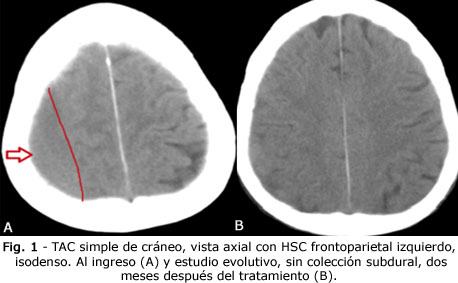

Se le realiza tomografía axial computarizada (TAC) de cráneo urgente; se aprecia un hematoma subdural crónico, de aproximadamente 21 mm de grosor, sin efecto de masa (Fig. 1 A).

Los dos últimos fármacos, los mantuvo hasta 3 meses después de haber ingresado. En el caso del antihipertensivo, se disminuyó la dosis una vez desaparecido el hematoma. Mantuvo ingreso durante 3 semanas. La cefalea desapareció y se continuó seguimiento en consulta externa. A los dos meses se realizó TAC evolutiva y no se encontró presencia de colección subdural (Fig. 1 B).